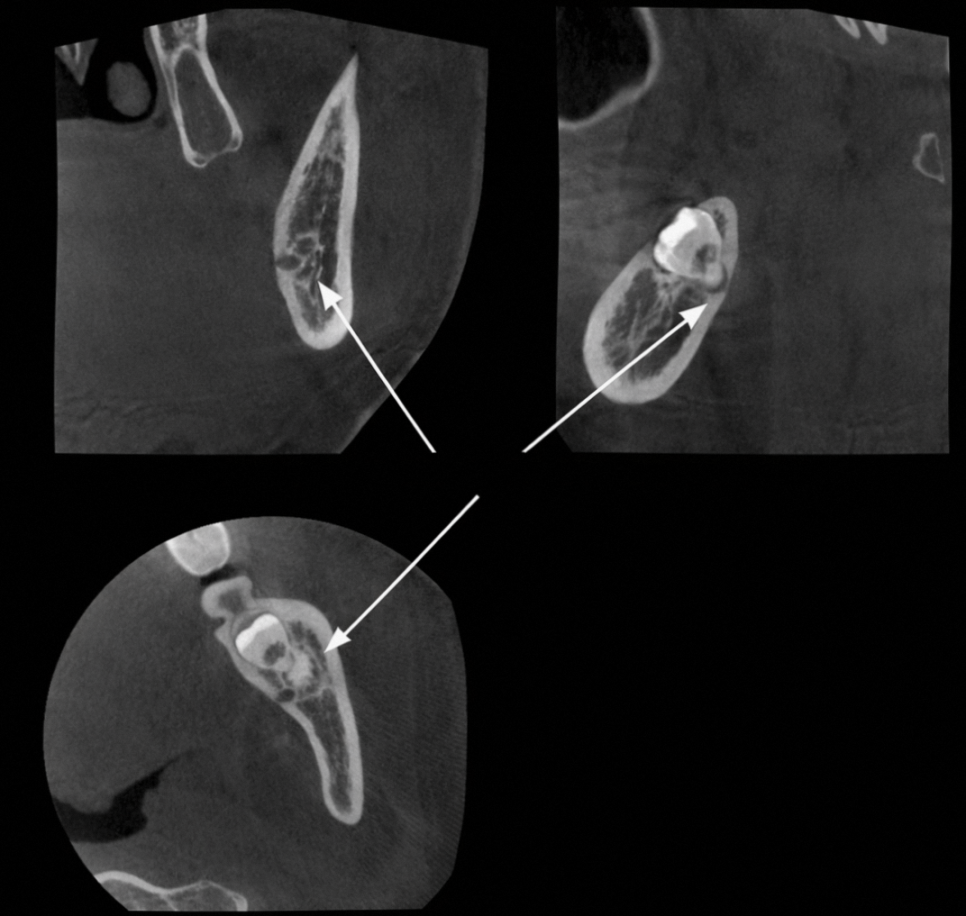

만일 신경과 가깝다고 의심되는 경우에는

CT 촬영을 통한 분석이 필요합니다.

이를 통해 치근의 정확한 형태와 방향

신경관의 거리 및 접촉 여부,

주변 뼈의 두께와 구조물의 위치 등

이 정보들을 충분하게 확보되었을 때

발치 계획을 정밀하게 수립할 수 있으며,

예상치 못한 상황을 최소화할 수 있습니다.

사랑니 발치에서도,

까다로운 곳은 하악입니다.

그 이유는 하치조신경 때문인데,

아래턱뼈 안을 지나가는 신경 조직으로,

하악에 관련된 감각을 담당합니다.

매복 사랑니의 뿌리는 위치 관계상

하치조신경과 근접하게 위치한 경우가 많고,

때로는 조직을 감싸듯 맞닿을 때가 있습니다.

만일 발치 과정에서 자극이 전달되면,

감각 이상이나 마비가 발생합니다.